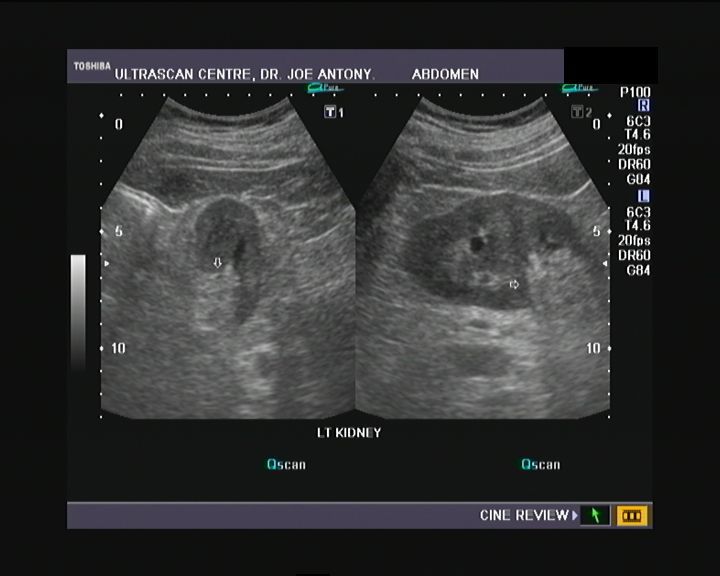

The left kidney in this male child shows a prominent column of renal cortex in the middle third of the kidney. This column of tissue is seen encroaching on the renal sinus, with the renal contour (outer margins of the left kidney) appearing normal. Color Doppler images of the left kidney show normal vascular pattern in the column. The echogenicity and echotexture of the column of tissue appears similar to the adjacent renal cortex. These ultrasound images and the sonographic findings are typical of what is called hypertrophied column of Bertin. The current terminology for this benign normal variant is junctional parenchyma. This new term for a long understood normal variant, is used as the renal tissue in the column of Bertin does not show any evidence of hypertrophy. The tissue in the junctional parenchyma/ hypertrophied column of Bertin is absolutely normal renal parenchyma and contains renal cortex, pyramids and septa or columns of Bertin. the renal tissue in the column is continuous and merges with the adjacent cortical tissue of the kidney. The column of Bertin is most commonly seen involving the left kidney as in the case above.